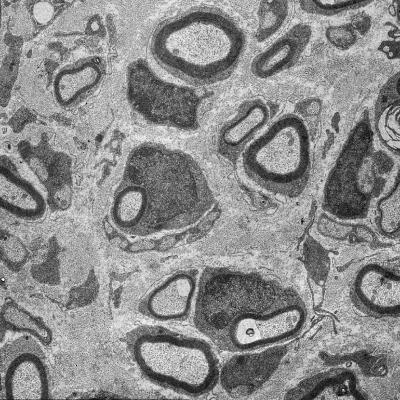

This is an electron microscope image of a cross-section through a mouse nerve: following injury, the myelin sheath of numerous regenerated nerve fibers is too thin.

(Photo Credit: MPI of Experimental Medicine)

From their cell bodies to their terminals in muscle or skin, neuronal extensions or axons in the peripheral nervous system are surrounded along their entire length by glial cells. These cells, which are known as Schwann cells, envelop the axons with an insulating sheath called myelin, which enables the rapid transmission of electrical impulses. Following injury to a peripheral nerve, the damaged axons degenerate. After a few weeks, however, they regenerate and are then recovered with myelin by the Schwann cells. For thus far unexplained reasons, however, the Schwann cells do not manage to regenerate the myelin sheaths completely. Thus the function of damaged nerves often remains permanently impaired and certain muscles remain paralysed in affected patients.